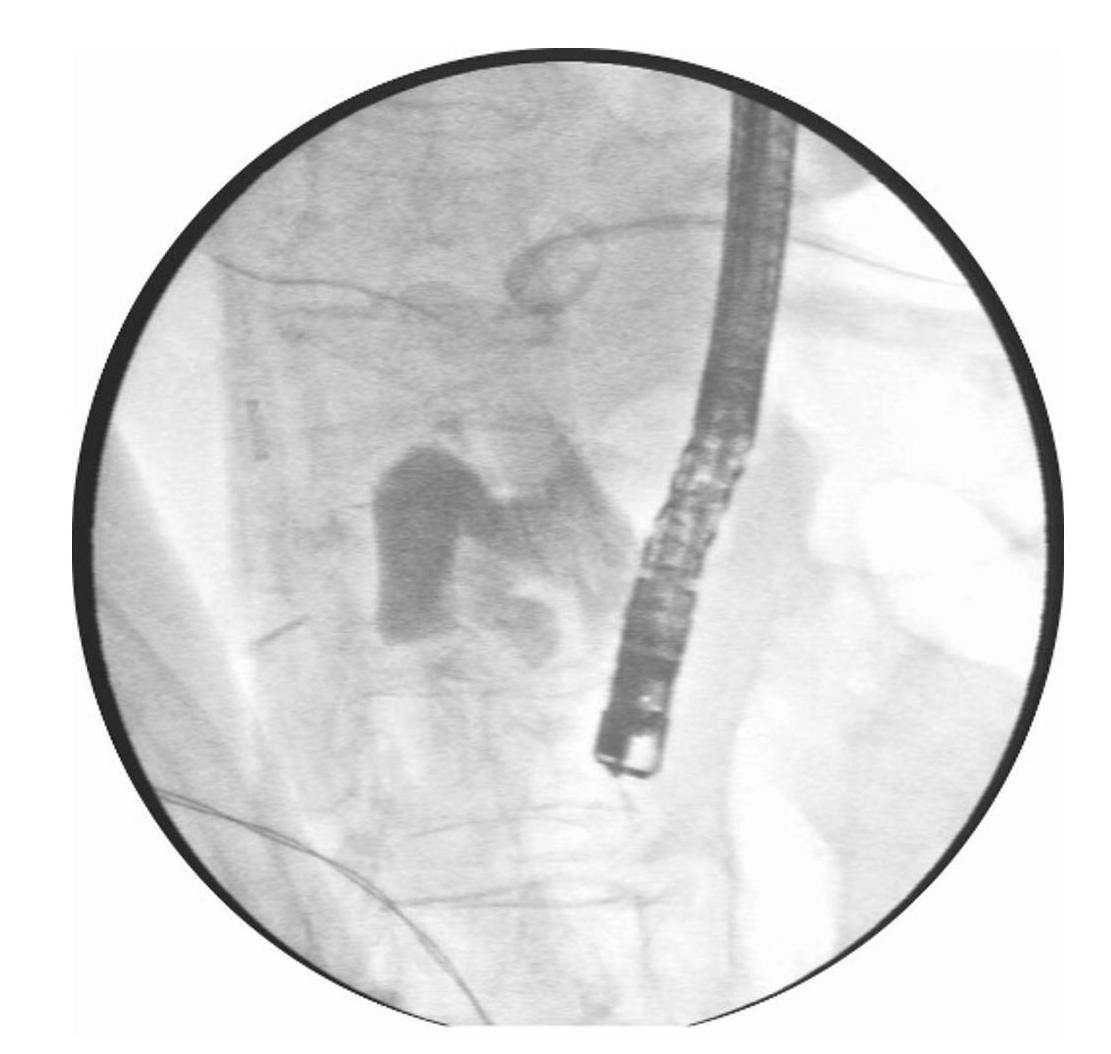

治疗经过:为解除胆总管梗阻,患者入院后完善相关检查后于2023年4月20日行ERCP。术中患者取仰卧位,以治疗肠镜带透明帽进镜,胃大弯处可见吻合口,幽门保留状态。经幽门进入十二指肠降部,内侧可见既往手术瘢痕,而未见十二指肠主乳头(图1),自此更换十二指肠镜进镜至十二指肠降部,于降部内侧也未见主乳头。助手经 PTCD 引流管注入造影剂,肝内外胆管显影并见明显扩张,胆总管内见多发充盈缺损影,考虑为胆总管结石,最大直径为0.8 cm,而造影剂未能进入十二指肠腔 (图2)。沿PTCD引流管置入导丝至胆总管内,在透视下超选导丝无法进入十二指肠腔,考虑胆管开口狭窄明显或闭塞(图3)。以针状刀于降部内侧瘢痕上方行开窗术后,可见胆汁流出,切开刀辅助导丝插管进入胆总管内(图4),沿导丝置入扩张球囊扩张胆管开口0.6 cm,置入取石网篮分次取出大量黄褐色结石,生理盐水冲洗胆管后,再次造影见胆总管下端狭窄显著,遂沿导丝置入1枚胆管塑料支架 (8.5 F×7 cm)。患者术后恢复良好,未出现ERCP术后相关并发症,于2023年4月25日顺利出院。出院后随访患者未诉特殊不适,并于术后2周顺利拔除 PTCD引流管。

图4进行了1次新颖的NKF

Figure4A novel NKF was conducted

在本例中,如何找到胆管开口位置异常重要。用导丝经过PTCD引流管置于胆总管下端后进行盲插,同时于十二指肠镜直视下可见被导丝顶出的黏膜即可考虑为胆总管开口处。紧接着,采取类似于 NKF的方法,用针状刀于前述位置处做一纵行小切口,逐层切开黏膜。当胆汁从切口处流出时,考虑导丝已成功进入胆管。通过人工造瘘的方式,在导丝辅助下成功完成了此次的胆管插管,从而进一步采用取石网篮取出患者的胆管结石。